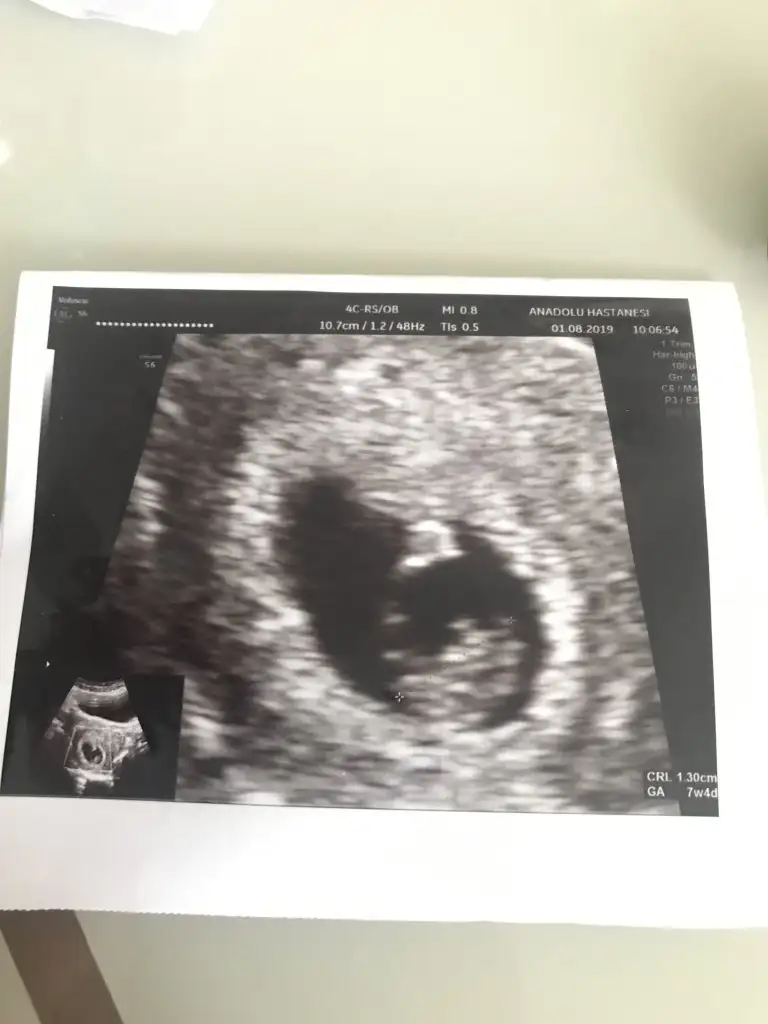

MaşaAllah elleri ayakları belli annem olsa oğlan o derdi :) ona göre 3 aylıkken kızların elleri ayakları anca belli olurmuş tamamen hurafe :))Kızlar buda benim bebeşimdoktordan geldim. Herşey yolunda çok şükür. Kalp atışını dinledik. Nasıl bir mutluluk. Allah hepimize sağsağlim kucaklamayı nasip etsin. Doktor sat ı 10 hazirana çekti. Normalde 26 mayıs tı son adet tarihim. Geç döllenme olmuş dedi. Yaklaşık 2-3 hafta kadar.

Kızlar buda benim bebeşimdoktordan geldim. Herşey yolunda çok şükür. Kalp atışını dinledik. Nasıl bir mutluluk. Allah hepimize sağsağlim kucaklamayı nasip etsin. Doktor sat ı 10 hazirana çekti. Normalde 26 mayıs tı son adet tarihim. Geç döllenme olmuş dedi. Yaklaşık 2-3 hafta kadar.